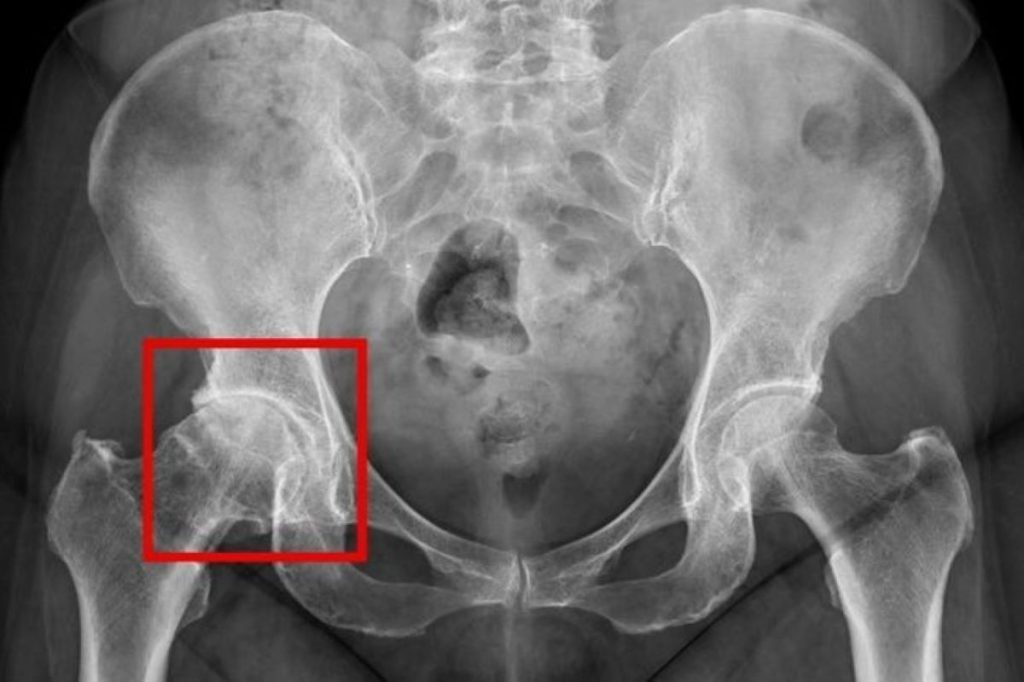

髖關節疼痛初期治療上多採「保守治療」為主,包括休息、使用消炎止痛藥物、熱敷、電療或減重,藉此減輕疼痛、維持關節活動度及延緩退化。針對嚴重髖關節退化的病人,人工髖關節置換手術為主要治療方式,醫師會在術前透過X光等影像檢查,評估關節磨損程度與骨骼狀況,以規劃適合的手術方式。